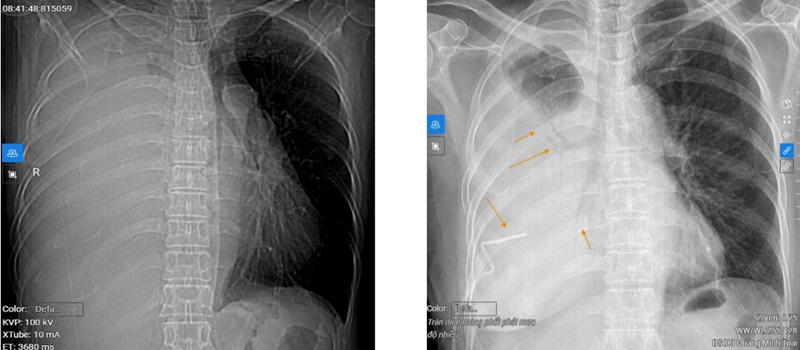

Bệnh chỉ biểu hiện rõ khi đã tiến triển với những triệu chứng: Ho có đờm lẫn máu, một thời gian sau bệnh nhân có thể gầy sút cân, mệt mỏi, thở nông, khàn giọng, khó nuốt, đau xương, thở khò khè và tràn dịch màng phổi. Lúc này, bệnh đã ở giai đoạn muộn và bệnh nhân thường tử vong rất nhanh chỉ sau 6 tháng - 1 năm.